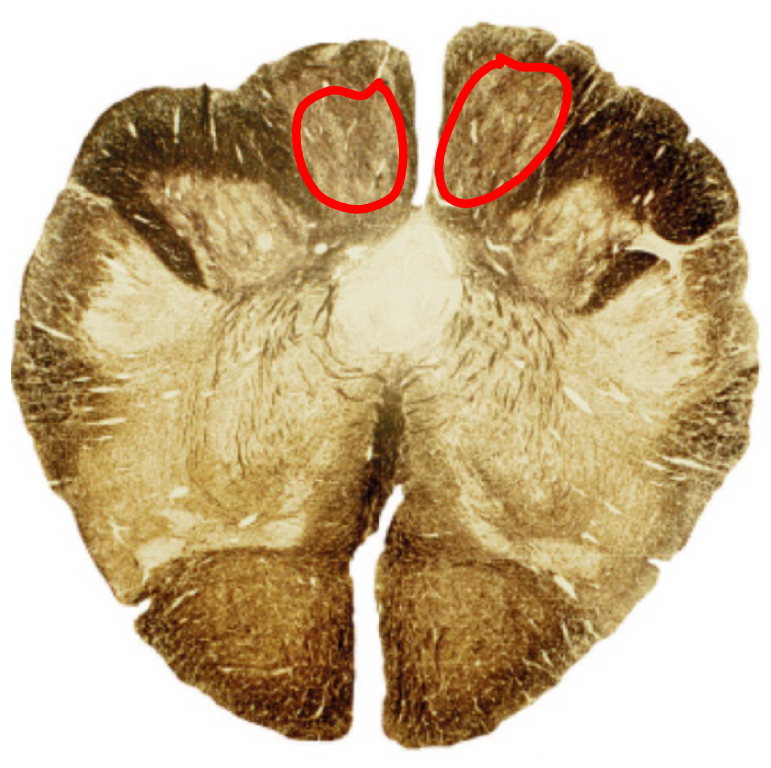

pontocerebellar fibers middle pons

corticospinal fibers middle pons

trigeminal nerve middle pons